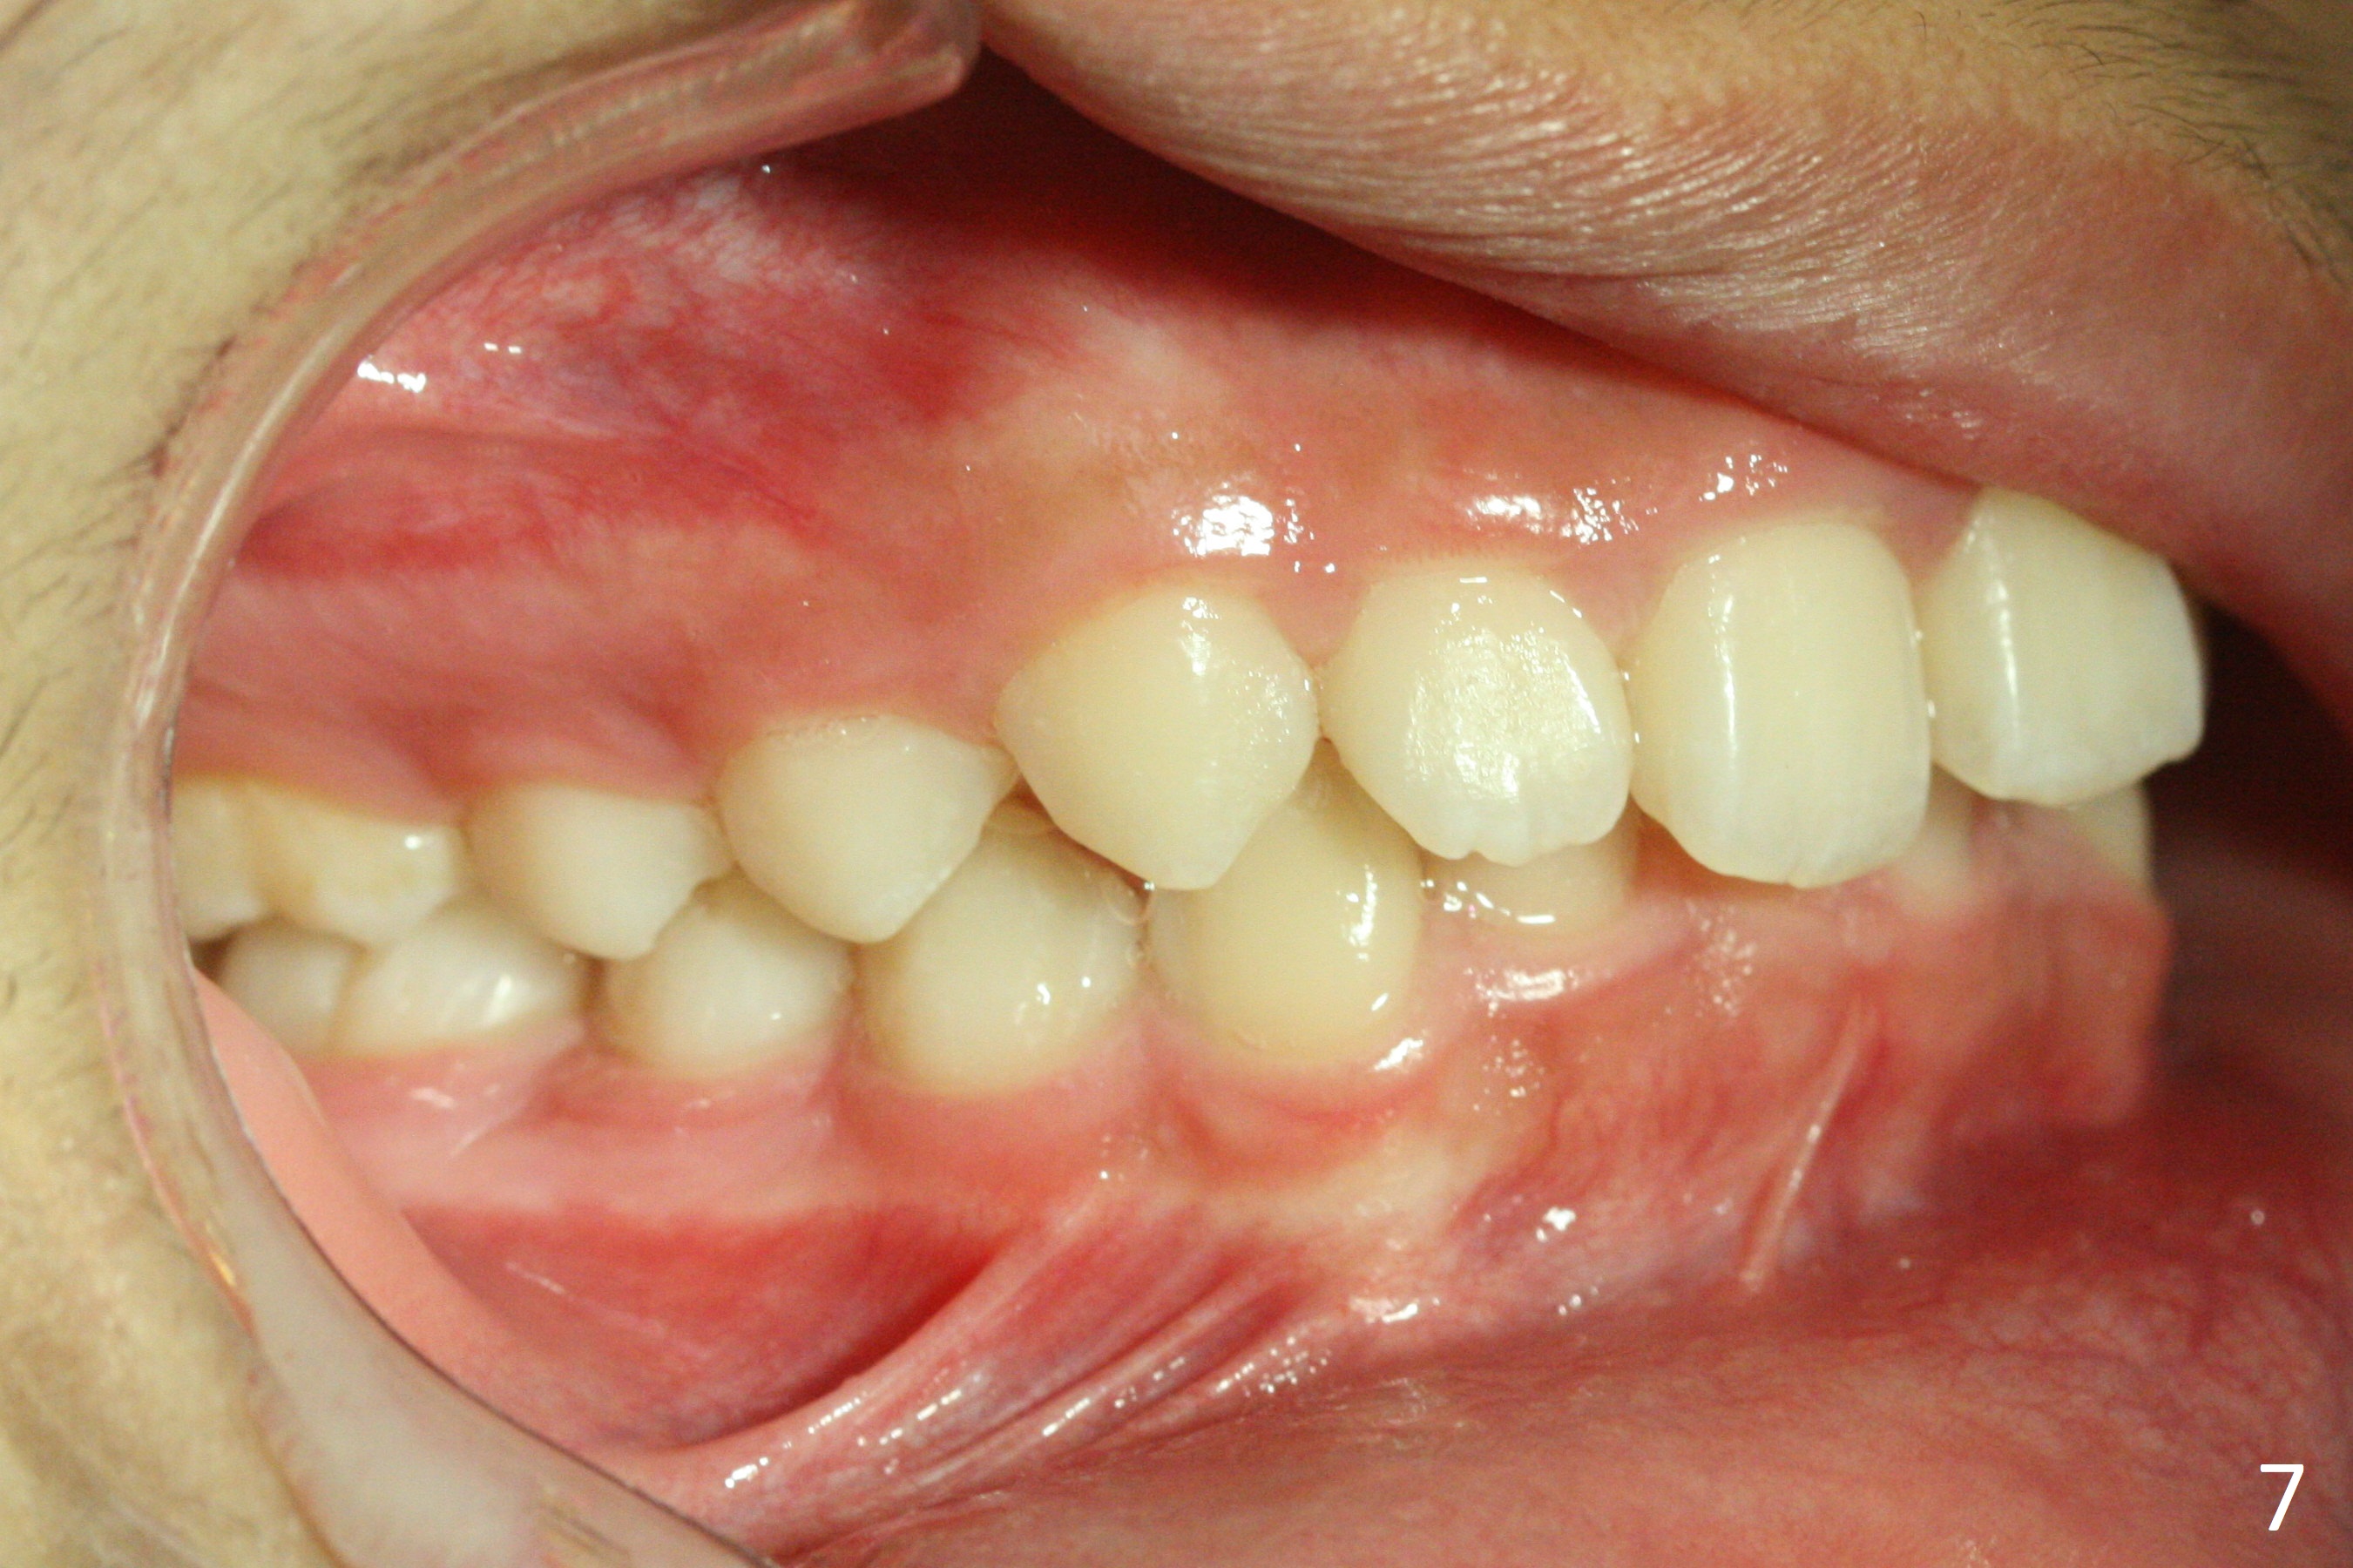

A 12-year-old woman has normal facial profile (Fig.1-6,12) and crowded dentition (7-11). Because of erupting 2nd molars (Fig.10,15), it is difficult to place rubber separators between U6/7. Copper ones are used instead (Fig.15 ^). Crowding and narrow arches (Fig.13,14) may be associated with the enlarged right Inferior Nasal Concha (Fig.15 *).